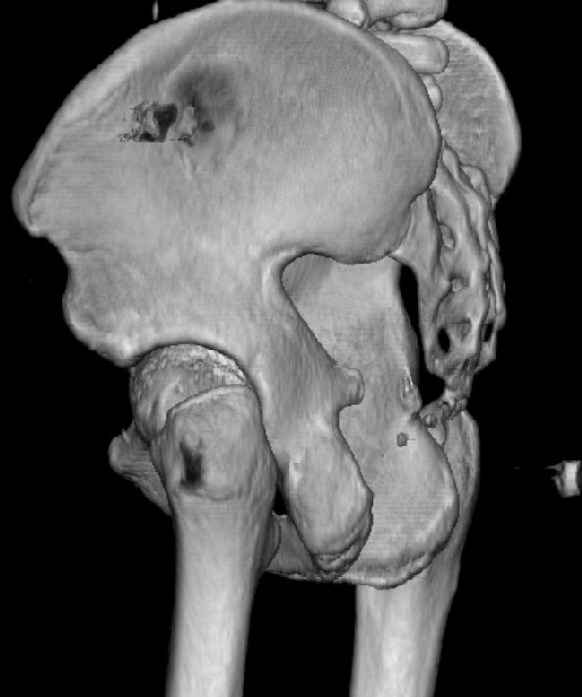

While not claiming to have the best 3D brain around, it appears to me from the limited images available, that the caudal segment is stable from the symphysis to the SI joint on the fracture side. I would love to see the rest of the transverse CT images to see where the fracture line actually exits posteriorly on both the inner and outer tables of the ilium. In my hands,

assuming that the femoral head has followed the cephalad (dome) fragment, I would use an ilioinguinal approach and take down the fracture line from anterior to posterior, distracting with a lamina spreader, if necessary, to clean out and inspect the joint. I would then reduce the cephalad fragment to the caudal fragment using jungbluth or farabeuf clamp and screws and then apply a plate and screws. If the fracture exits posteriorly would you then favor an additional posterior approach to clean out and reduce from that side?

My concept is that what I am after is restoring the anterior portion of the acetabular ring to the superior dome portion to re-establish the containment of the femoral head in an intact "horseshoe". Is this accurate?

Some more images. Does it help to guess which part of the acetabulum is displaced?

Normal appearing SI joints and a healed posterior column limb... my bet's on caudal segment displacement.